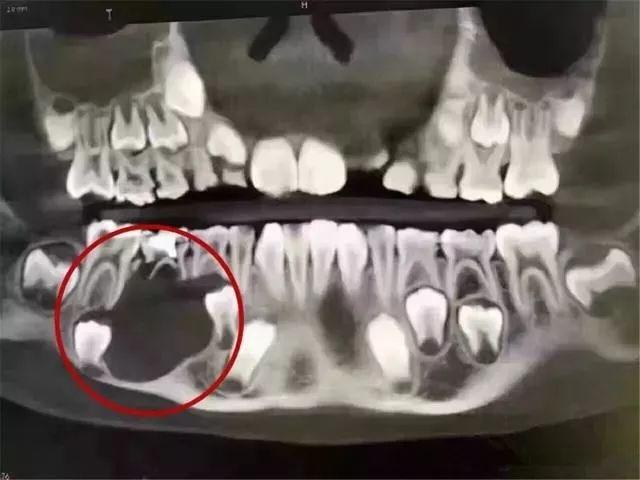

很有可能会导致乳牙提前脱落,这样会导致局部颌骨发育不足,缺牙的位置可能会因为旁边的牙齿移位导致部分甚至全部被占位,只至于恒牙错位萌出。而新牙的牙胚就在乳牙的压根下,乳牙反复发炎会影响到新牙的萌出。